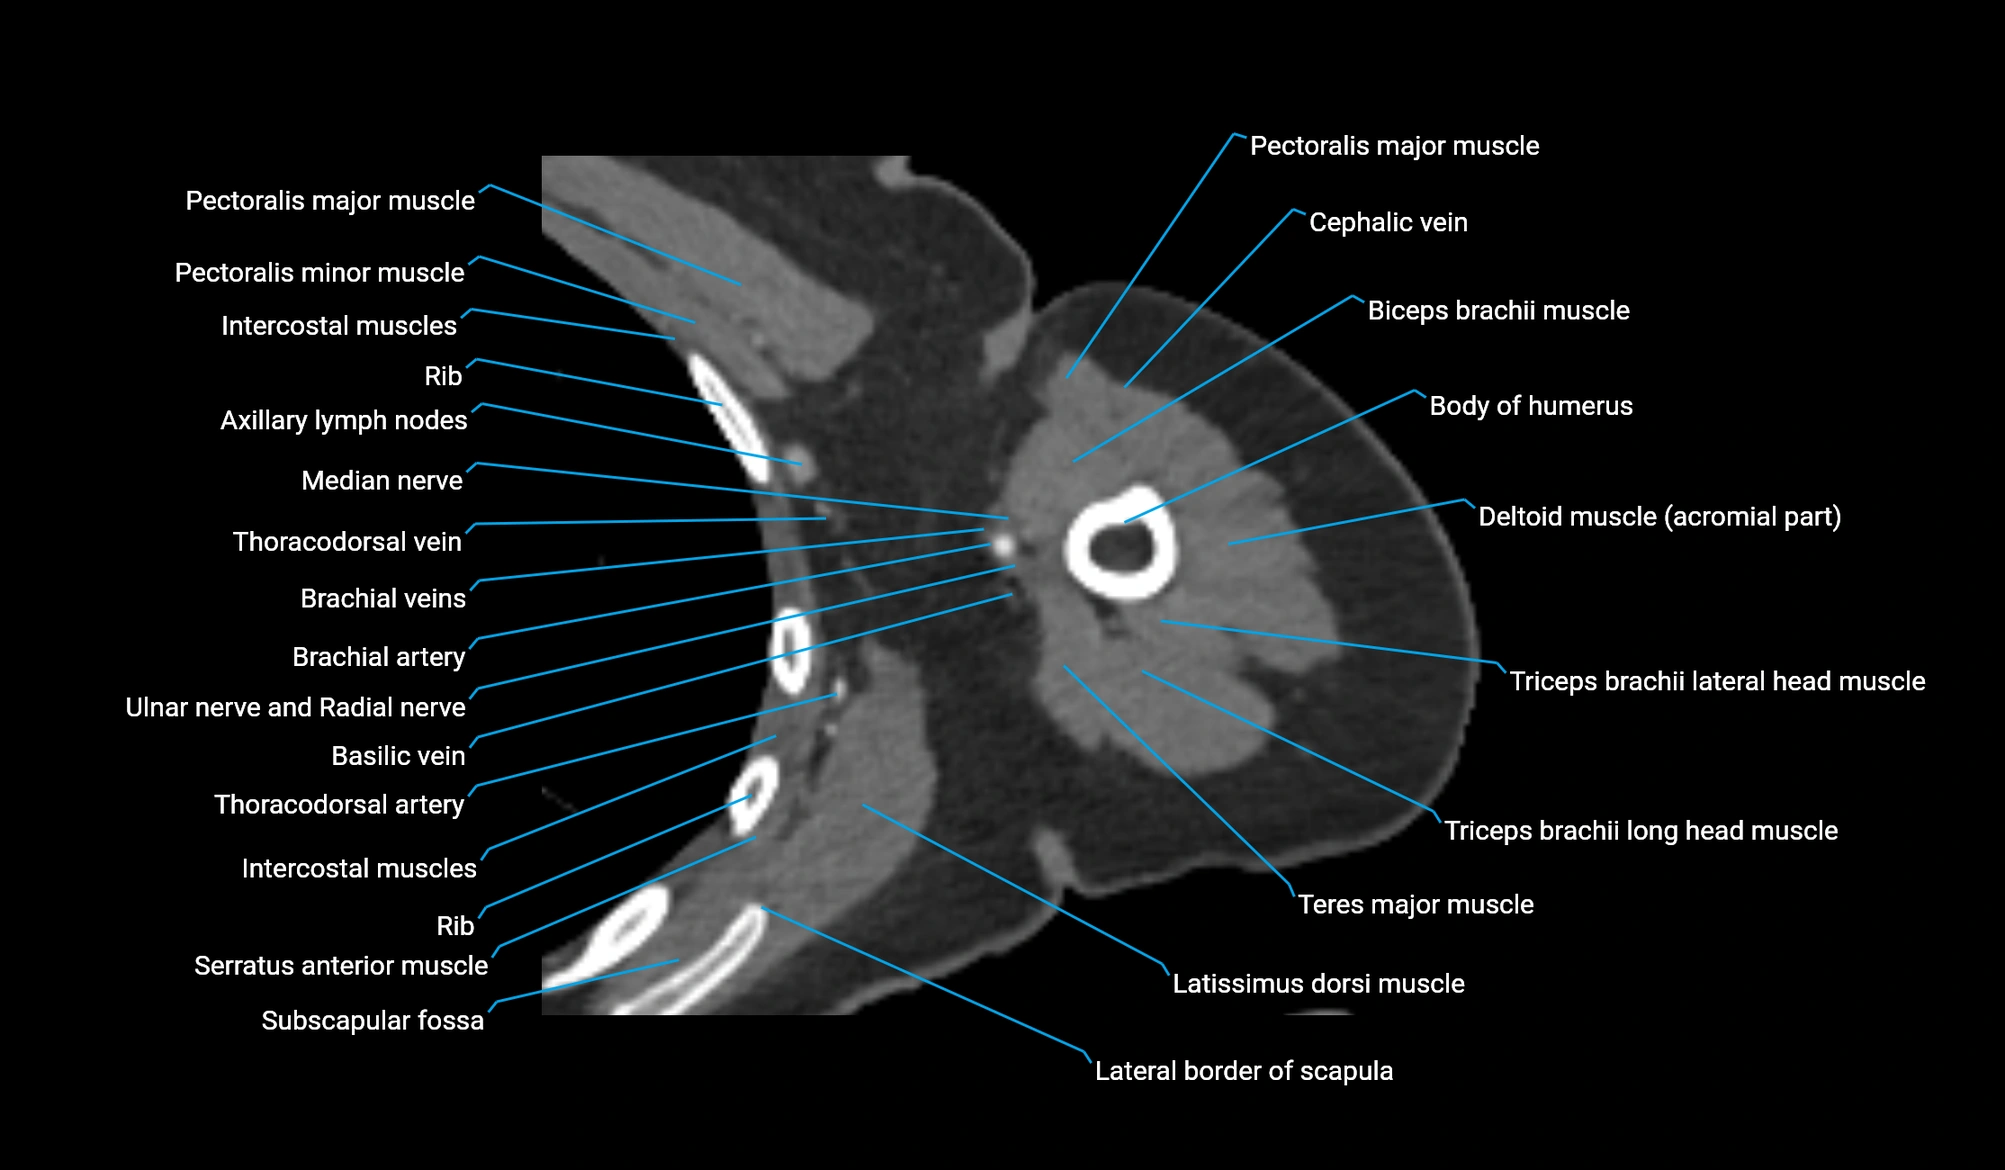

CT image